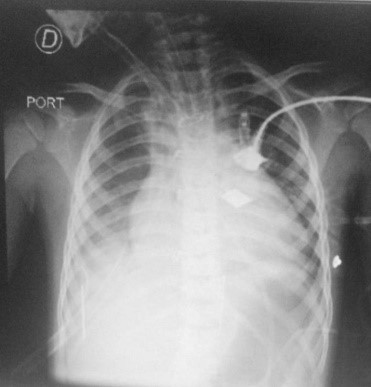

Figura 2: Radiografía de tórax al ingreso a unidad de cuidados críticos pediátricos

Radiografía realizada en el postoperatorio inmediato cardiovascular

Paciente masculino de 4 años, peso real 20 kg, con diagnóstico prenatal de enfermedad de Ebstein severa, con score Great Ormond Street Echo (GOSE) grado 3, cardiomegalia y cianosis, ingresó a sala general para cursar internación preoperatoria de cirugía cardiovascular programada. A continuación se presenta la placa radiográfica al mes de nacimiento, cursando internación en sala de neonatología (Figura 1). Mes previo a la intervención quirúrgica se realizó un ecodoppler cardíaco, que informó: Displasia severa de la válvula tricúspide, valvas engrosadas, con inserción distal marcada de la valva septal con adherencia de la misma al septum interventricular, ventrículo derecho (VD) anatómico 45 mm, VD funcional 18 mm (38 %), índice de GOSE 1.2 (Grado 3), comunicación inter-auricular (CIA) amplia (16 mm), con cortocircuito bidireccional a predominio derecha-izquierda. Al siguiente día del ingreso, se realizó la cirugía de Glenn y resección parcial de lonja auricular derecha con clampeo, la cirugía duró 7 horas, el tiempo de circulación extracorpórea (CEC) fue 70 minutos, ingresó a la unidad de terapia intensiva (UTI) intubado donde se lo vinculó a ventilación mecánica invasiva (VMI) y se entregó ONI a 20 ppm, por presentar presión arterial pulmonar mayor a 25 mmhg y saturación de pulso 50 %. El paciente presentó drenaje mediastinal, pleural y sonda vesical, cables de marcapaso transitorio auricular y ventricular. Se administró milrinona, dobutamina, y se transfundió una unidad de glóbulos rojos. Para la administración de VMI se utilizó el respirador Dräger Evita V300, en modo pediátrico. El modo ventilatorio que se utilizó fue presión control, ventilación mandatoria intermitente sincronizada (PC-SIMV), la presión soporte y presión inspiratoria configurada por el operador estuvo destinada a entregar volumen corriente de 6 ml/kg peso real del paciente. Para la entrega del ONI se utilizó el dispositivo Vaso Kinox de la empresa Air Liquide Healthcare, se comenzó con una entrega de 20 ppm. La dosis entregada se controló a través de sensor proximal al paciente conectado en la rama inspiratoria del circuito ventilatorio, visualizado a través de un monitor BedFont (Box Nox2). Se presenta a continuación la placa radiográfica del paciente una vez ingresado a unidad de cuidados críticos (Figura 2). Cursando segundo día de postoperatorio (POP) el paciente permaneció sin sedación, respirando en modo espontáneo, y con inotrópicos en descenso. Persistió la HTP evidenciada por ecocardiograma. Se realizó gasometría de control, y en acuerdo con los servicios de atención involucrados se decidió desvincularlo de la VMI, cumpliendo un total de 38 horas, posterior a la extubación se vinculó a cánula nasal de alto flujo (CNAF) (se utilizó cánula nasal Optiflow junior de Fisher & Paykel) continuando el tratamiento con ONI. Para medir precisamente las ppm entregadas se colocó un catéter nasofaríngeo (Nelaton n.º 8 cortada de 7 cm) conectada al sensor (Figura 3). Los parámetros requeridos en CNAF fueron 35 L/min y 85 % de fracción inspirada de oxígeno (FI02). Se continuó entregando la misma dosis de ONI a 20 ppm. Diariamente se registró la entrega de ONI por CNAF, teniendo en cuenta la diferencia existente entre la entrega de ppm configurada en el visor Kinox y la entregada en nasofaringe detectada por el catéter y expresada en el monitor, debido a la entrega de ONI por CNAF es un sistema abierto con presencia de fugas se observó una diferencia en la medición, la cual no ocurrió al entregarlo a través de un sistema cerrado como lo es la VMI con tubo endotraqueal (Figura 4). El ONI fue entregado mediante CNAF hasta el 4º día POP, cumpliendo 87 horas, se decidió suspender ONI con los siguientes parámetros clínicos, 107 frecuencia cardiaca (FC), 15 frecuencia respiratoria (FR), 90 % saturación de pulso (SAT), 15 L/min – 60 % FIO2, 12,9/22 ppm. A las 3 horas de suspender el ONI se decidió reconectarlo debido a la presencia de cianosis, y desaturación, SAT 69 %, 132 FC, 25 FR, al constatar el efecto rebote, se modifican los parámetros de CNAF a 25 L/min, 70 % FIO2, y se reconectó nuevamente ONI a 12 ppm. Una hora posterior a la reconexión, se logró estabilidad clínica, y los parámetros de CNAF y ONI no fueron modificados por 24 horas, al día siguiente se descendió los parámetros de ONI y CNAF progresivamente, y al día 6° POP se suspendió la administración de ONI y CNAF, y se desescaló a cánula nasal de bajo flujo (Figura 5). Parámetros previos a la suspensión de ONI y CNAF: 120 FC, 18 FR, 82 % SAT. CNAF: 15 L/min, 60 % FI02. ONI: 0,8 ppm (4 ppm configurado), 60-52 % FIO2. Cumpliendo 126 horas de ONI total y 91 horas de CNAF. Al día 15º POP se retiró el aporte de oxigenoterapia, y al día 18º, se realizó ecocardiograma que informó Glenn normofuncionante y CIA amplia con cortocircuito bidireccional. El paciente fue externado. A continuación, se presenta una tabla que refleja las horas brindadas por cada terapéutica en relación a la entrega de ONI (Tabla 1). Todos los datos brindados fueron recabados de las planillas diarias del servicio de kinesiología, y evoluciones diarias del servicio de cirugía cardiovascular, diagnóstico por imágenes y médicos de UTI.